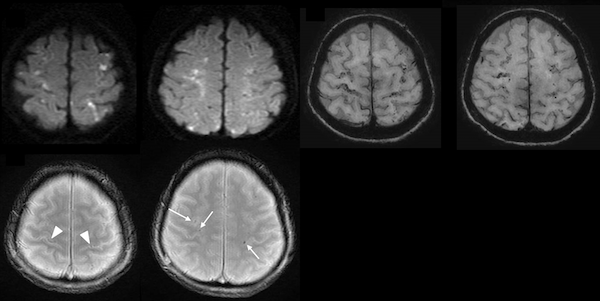

5. 癌関連脳卒中Cancer Associated Stroke CAS (Trousseau症候群)

全身性に癌があると凝固、線溶系を活性化し、多発する小梗塞巣をきたすことが知られています。また非細菌性血栓性心内膜炎NBTEで形成された血栓が脳動脈を閉塞することもあります。当科ではCASの病態と治療法について研究しています。

6. 血管炎と脳梗塞、脳出血、限局性くも膜下出血

好酸球性肉芽腫性多発血管炎は、ACAとMCAの境界領域に散在する脳梗塞をきたし、その後数日して脳表微小出血およびくも膜下出血をきたすことを報告しています。炎症、白血球浸潤による微小循環障害、内皮損傷による微小出血と限局性くも膜下出血をきたすと考えられます(Int Med 2021)。